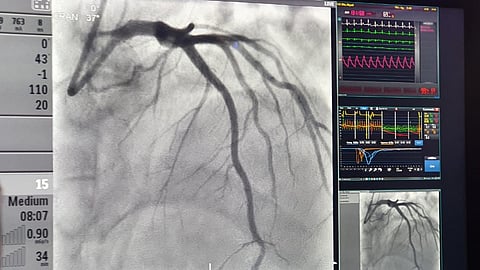

كشفت مدينة الملك سعود الطبية، ممثلة بمركز صحة القلب، عن استخدامها لتقنية (كوروفلو) الحديثة، حيث تم استخدامها لأول مرة على مستوى المملكة.

وأوضح مدير مركز صحة القلب بالمدينة د.مبارك الدوسري، بأن التقنية تستخدم لتشخيص نقص التروية بالشرايين الدقيقة في القلب، وتشخيص كامل لفيسولوجية القلب، ويكتشف ضعف الأوعية الدموية الدقيقة، ويساعد على علاجها؛ حيث تم تشخيص حالة مريض يعاني من ضعف الأوعية الدموية الدقيقة المتفرعة من الشرايين التاجية.

ونوه د.الدوسري، إلى أن نقص تروية الشرايين الدقيقة يُعد من المشاكل التي تصيب القلب وتتسبب بالألم، رغم سلامة الشرايين الرئيسية.